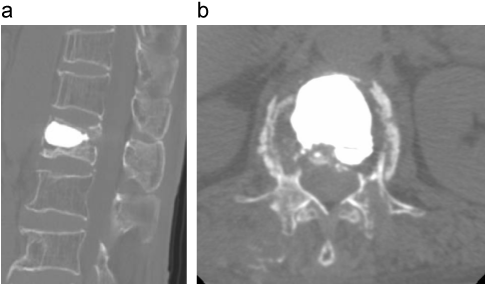

症例2の椎体形成術術後画像

骨癒合不全部に骨セメントを挿入する椎体形成術。椎体の後弯変形が復元している。

a:CT矢状断像

b:CT横断像

出典

img

1: 著者提供